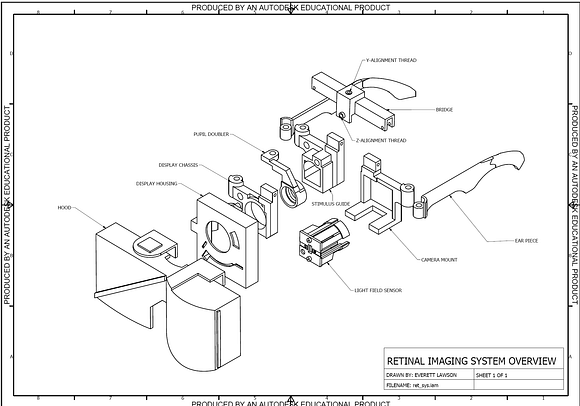

This system expands upon prior work by fully integrating the self-alignment architecture within the portable user interface. See patent on binocular coupling and presentation at Vodafone Wireless Innovation Prize.